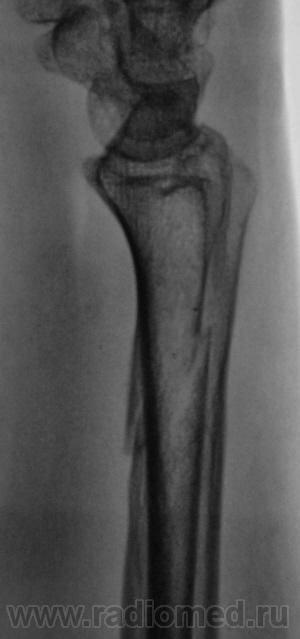

патологический перелом н\3 предплечья. Действительно без боковой проекции просто никуда!

Консолидированный нормальный перелом ))))))))))))))))) Просто гематома обызвествилась.

Что за причины быть ему патологическим? нормальный перелом, удовлетворительная консолидация

что имеется полость в проекции диафиза локтевой кости.

"Полость" - это игра теней.

Согласен, что перелом не патологический, скорее "геронтологический".